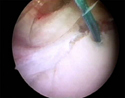

Βλάβη Bankart πριν και μετά απο την αποκατάσταση

επιχειλίος χόνδρος μετά απο την αποκατάσταση (0.25MB)